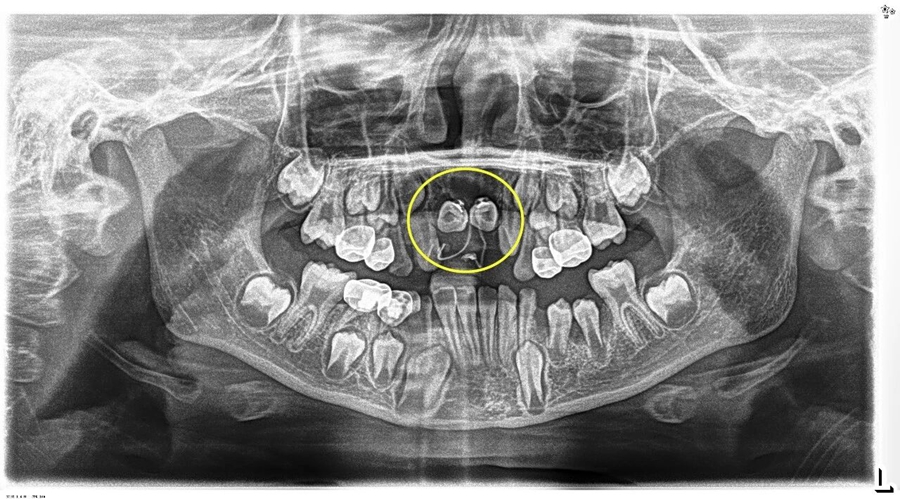

埋伏牙一旦發(fā)現(xiàn),應(yīng)及早處理。針對小胡的情況,口腔團隊在完成多生牙的拔除后,為埋伏牙粘接牽引裝置,通過溫和的正畸力對受影響的恒中切牙進行“牽引導萌”,"拉" 回正常生長軌道。

術(shù)后小胡恢復非常順利。第一次復查時,兩顆恒中切牙的舌側(cè)扣和彈性附件的影像,下圖可見: